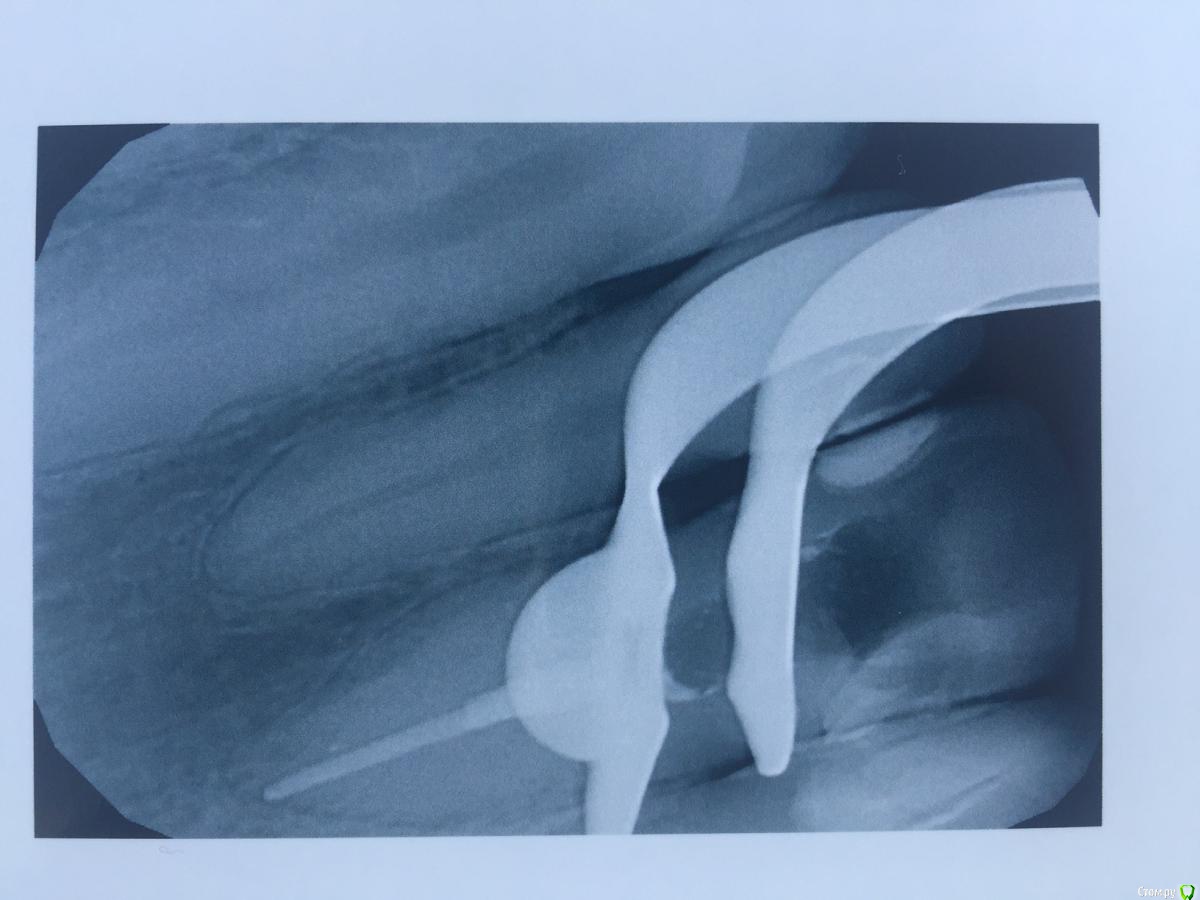

alina39 Опубликовано 9 декабря, 2016 Автор Поделиться Опубликовано 9 декабря, 2016 (изменено) Сделали новую КТ, подтвердился диагноз кистогранулема, почти киста по размерам.В прикрепленных - скриншот кт зуба.А главное боль не проходит, промыли и кальций положили неделю назад а боль не унимается, болит как рана и изредка дергает немного.Был один светлый период - 3 недели назад - когда зуб открыли, сказали полоскать и он неделю после этого не болел совсем, а потом все по новой. Изменено 9 декабря, 2016 пользователем alina39 Ссылка на комментарий

alina39 Опубликовано 9 декабря, 2016 Автор Поделиться Опубликовано 9 декабря, 2016 (изменено) покажите снимки на стадии леченияДругих снимков нет, сначала делали рентген, но на нем кисты не было видно, и потом вот два КТ: первый скриншот - это КТ 3 дня назад, а два других - 3 недели назад. Изменилось ли что-то за эти 3 недели? Изменено 9 декабря, 2016 пользователем alina39 Ссылка на комментарий